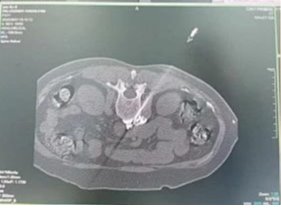

近日,鉴黄师 泌尿外科为一位复杂肾癌患者成功实施达芬奇机器人辅助下的复杂肾肿瘤切除术,术中精准切除肿瘤的同时保住了肾脏。标志着泌尿外科迈入机器人精准微创新时代,为患者带来诊疗福音。